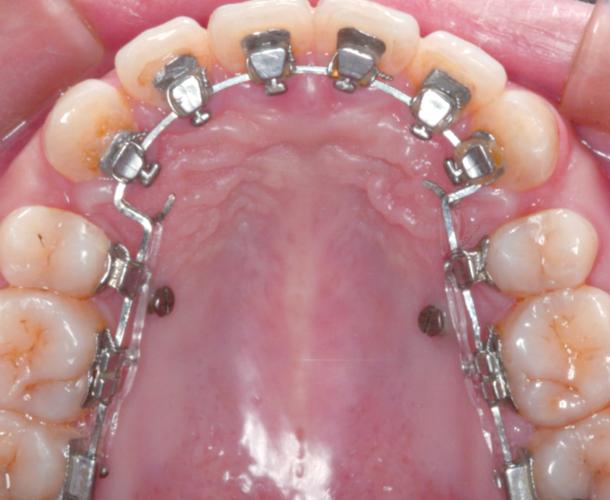

颌内牵引是指在同一牙弓内,通过牵引装置(如橡皮圈、螺旋弹簧、链状圈等)作用于单个或多个牙齿,实现牙齿的近远中移动、压低、伸长或扭转纠正,其图片特征主要包括:

- 牵引装置特写:口内直视图片中可见牙齿上粘贴的托槽、颊面管,以及连接于其间的橡皮圈(通常为“⟂”形或“8”形)或金属弹簧,例如使用镍钛螺旋弹簧关闭拔牙间隙时,图片中可清晰显示弹簧的压缩状态及两端与托槽的固定情况;

- 牙齿位置变化:治疗初期图片可能显示牙齿存在间隙(如拔牙后的间隙)或扭转(如上颌中切牙扭转),随着牵引进行,后续图片可见间隙逐渐缩小、扭转角度改善,牙齿移动至目标位置;